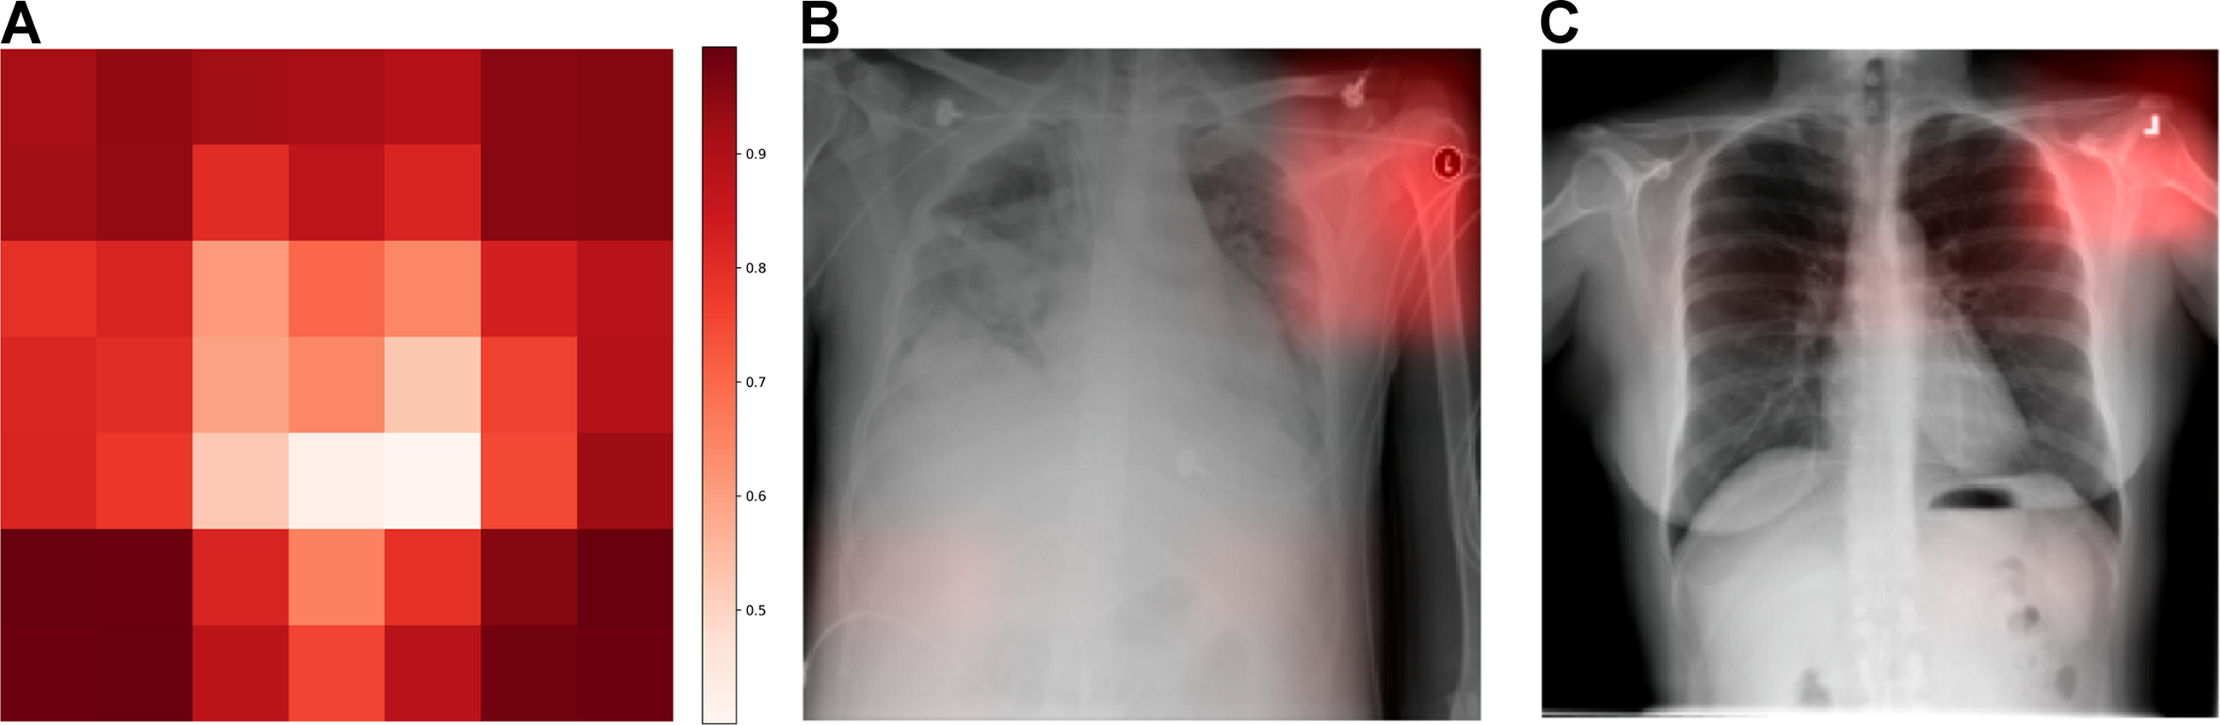

西奈山医院的研究员曾训练出一款诊断肺炎的“神级 AI”,准确率高得惊人。

但当科学家复盘时,却发现了一个荒诞的真相——这个 AI 根本没看肺部,它在看照片角落的“金属标签”。⑥

原来,重症患者通常无法下床,必须使用便携式 X 光机拍摄,这些机器会在影像上留下特定的金属标记。

AI 聪明地捕捉到了这个“相关性”:有金属标签 = 肺炎概率高。它只是一个高智商的“找规律机器”,一旦换了场景,这种“作弊式”的诊断就会造成致命误判。